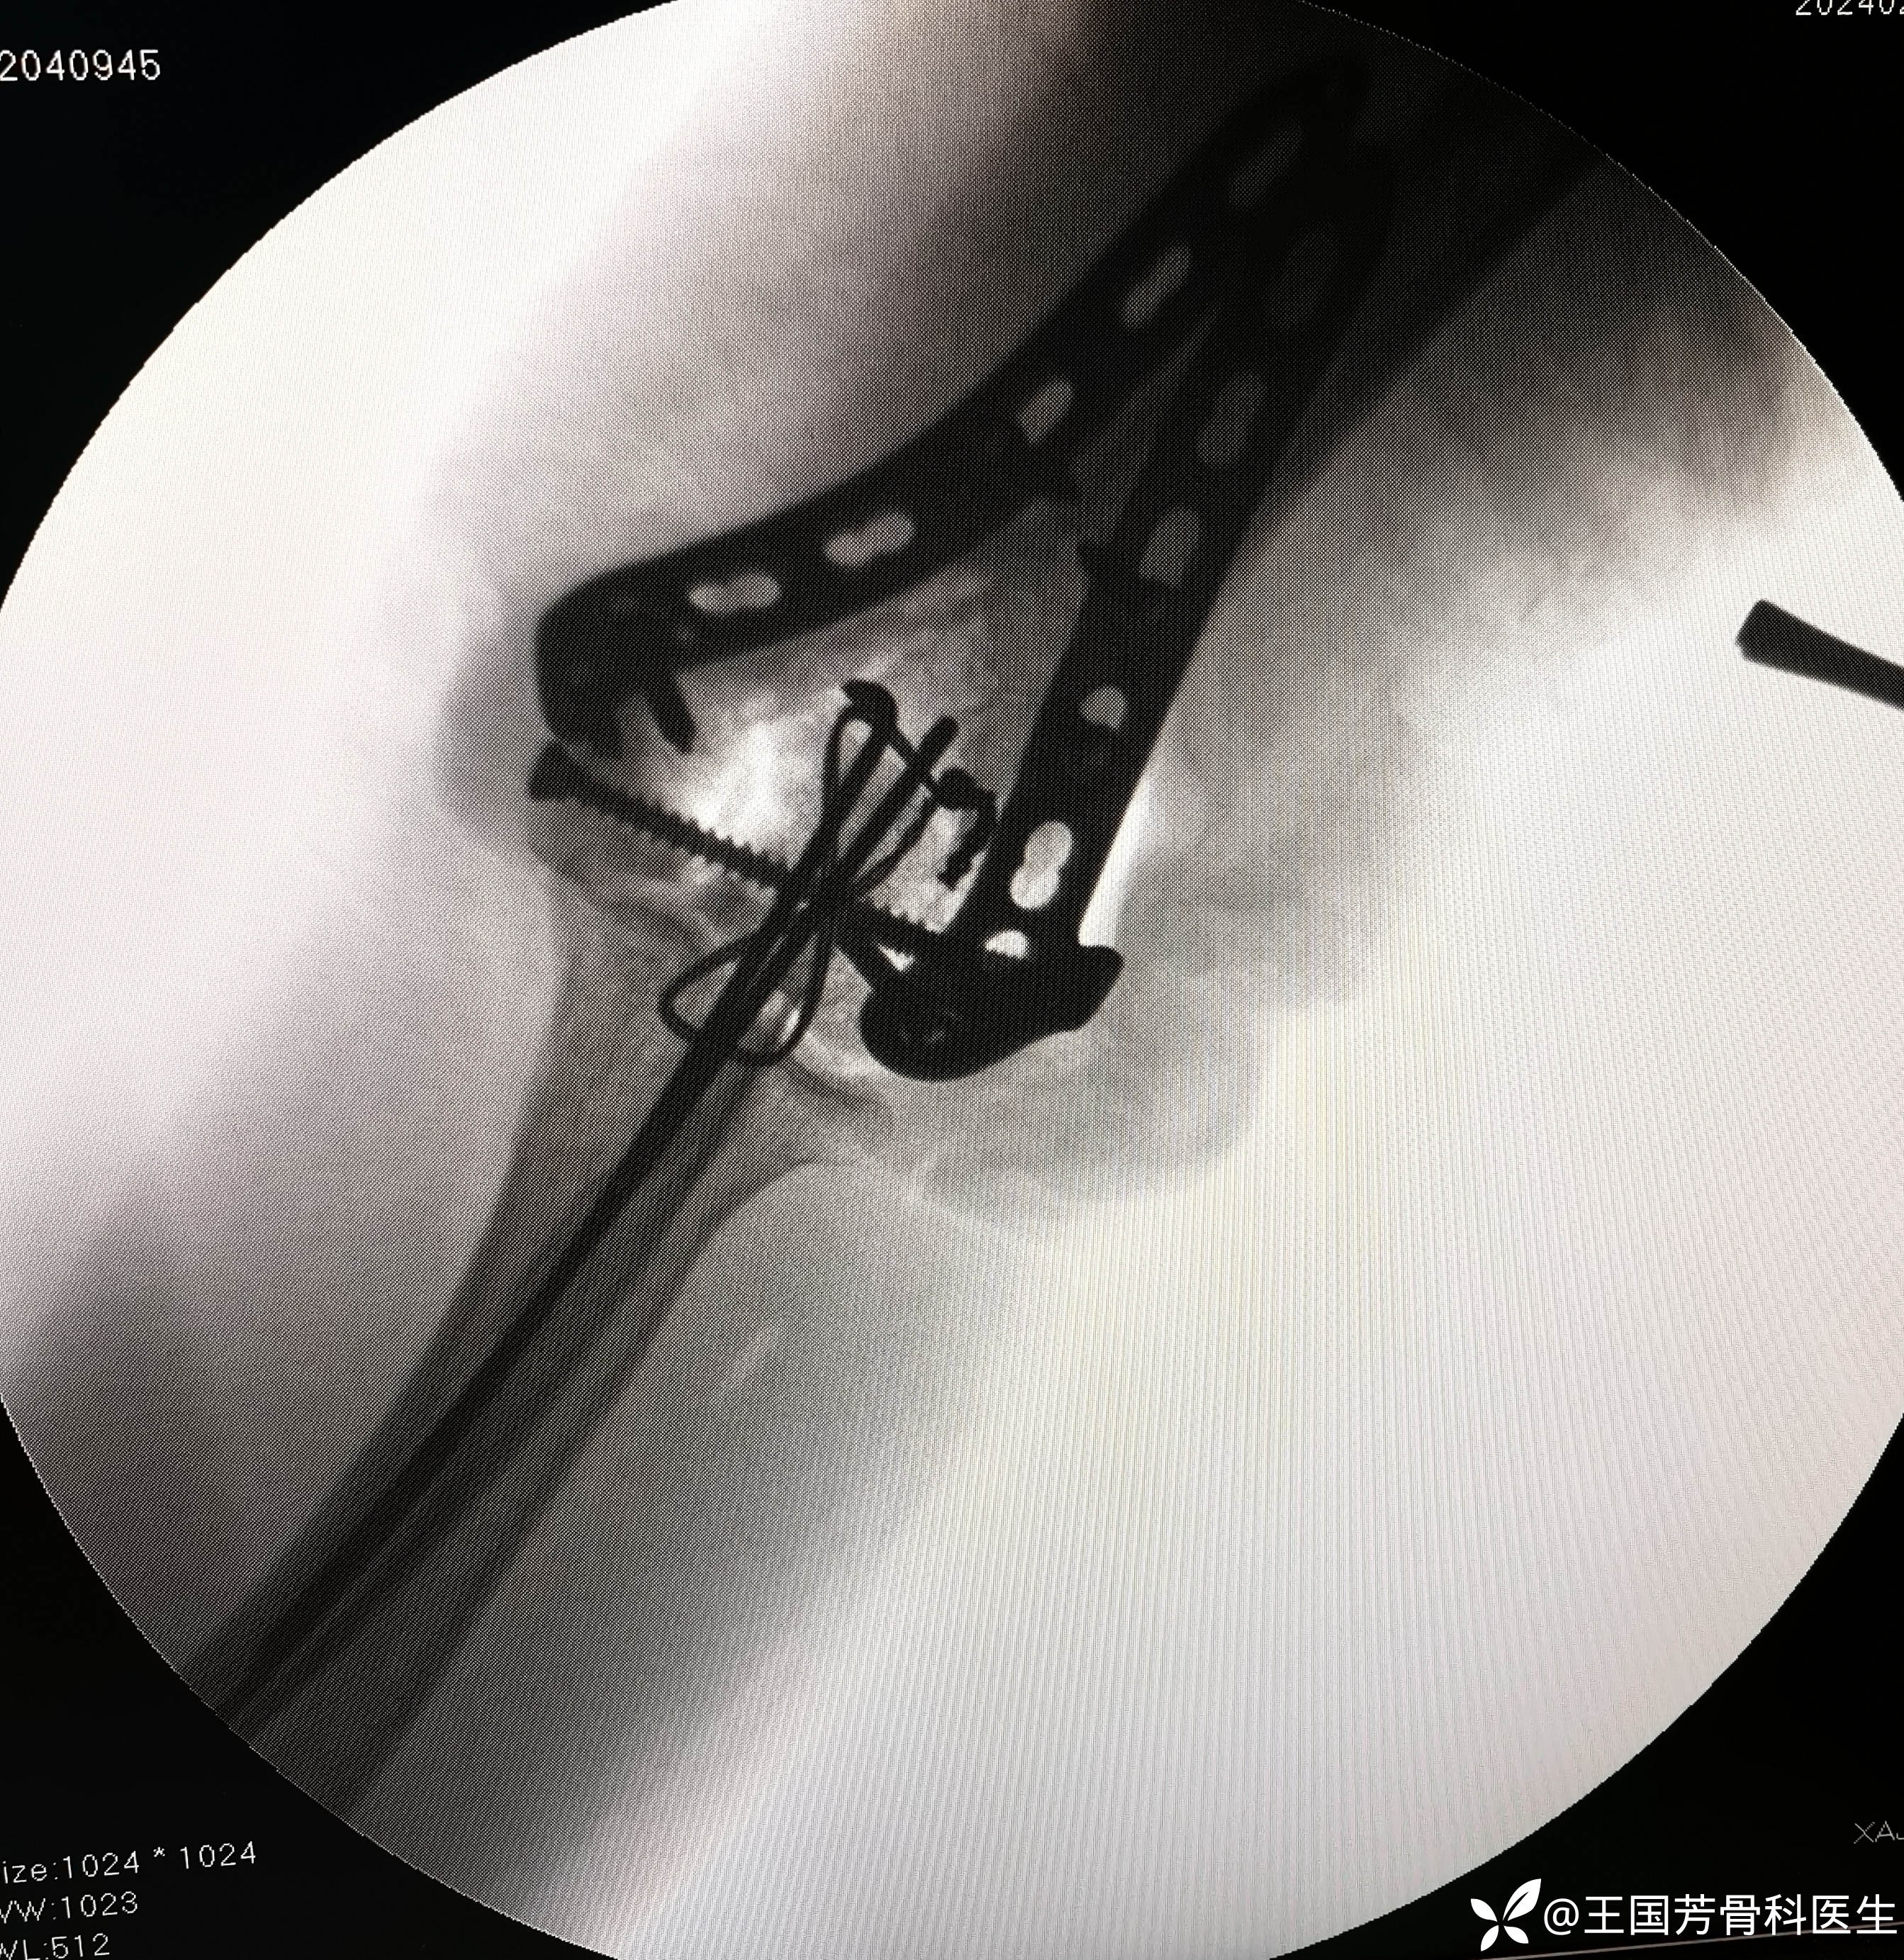

术后DR、CT

总结:1.肱骨髁间粉碎性骨折,watson一Jones“很难处理的少数几个骨折之一”一定认真对待;

2.术前检查,诊断,分型,手术时机,入路,内固定材料,复位顺序,主刀与助手配合等;

4.肱骨髁关节面一定解剖复位,双板坚强固定。